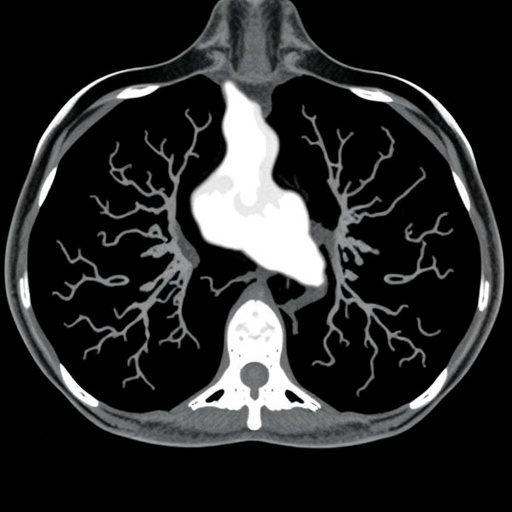

Traditionally, the cornerstone of treatment for BTCs has been surgical resection, which offers the only definitive chance for cure. However, given the anatomical complexity of the biliary tree and the propensity for early metastatic spread, only a fraction of patients are eligible for surgery. Moreover, the decision-making process is complicated by variable tumor locations and extent, necessitating an individualized assessment by a multidisciplinary team. This highlights the critical importance of integrating sophisticated diagnostic modalities, such as advanced imaging and molecular profiling, to accurately stage the disease and identify optimal treatment pathways.

Despite these advances, managing BTC patients remains a highly intricate process, reflecting the interplay of multiple factors including tumor biology, anatomy, patient performance status, and treatment-related risks. Multidisciplinary collaboration among hepatobiliary surgeons, medical oncologists, radiation oncologists, radiologists, and pathologists is essential to develop and execute a coherent treatment strategy optimized for each individual case. Furthermore, close coordination between locoregional and systemic therapies demands innovative clinical pathways to harmonize timing and sequencing of interventions.